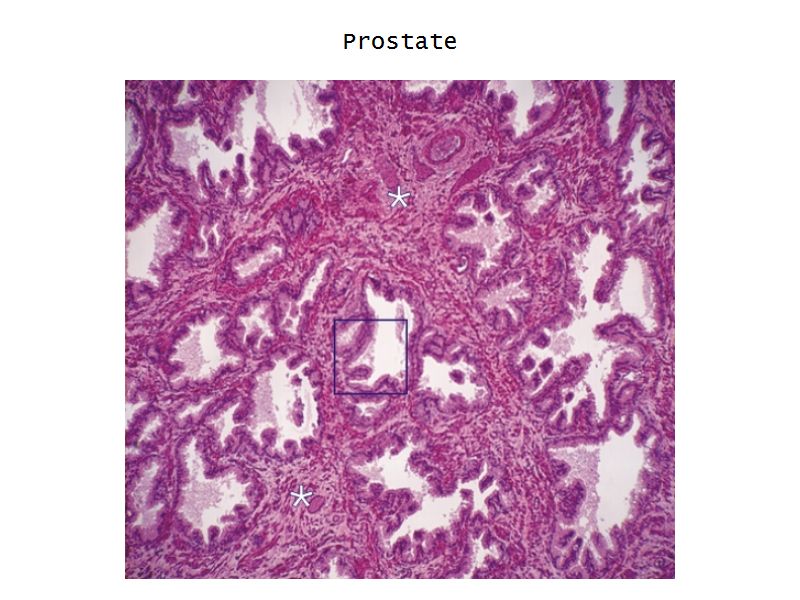

Prostate

Slide 80Prostate

- Surrounds urethra

- Largest accessory gland

- 30 - 50 branched tubuloalveolar glands

- Via excretory ducts

- Into urethra

Glands

- 3 concentric layers

- Around urethra

- Mucosal

- Submucosal

- Main

Capsule

- Fibroelastic capsule containing smooth muscle

- Divides into lobes

Concretions

- Sometimes in lumen

- Calcified

- Increase with age

Epithelium

- Simple columnar or

- Pseudostratified columnar

- Surrounded fibroelastic CT

- CT with rich vascular supply